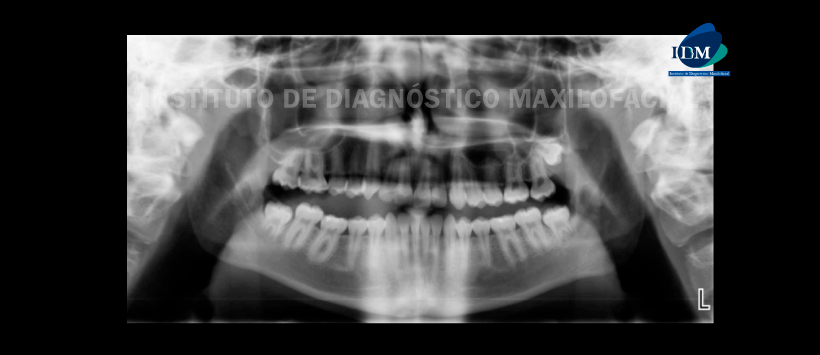

A la evaluación de la radiografía panorámica. Se evidencio que todos los terceros molares estaban presentes e impactados, excepto en el lado superior derecho donde faltaba el diente, con los terceros molares inferiores muy cerca de los canales alveolares inferiores (Figura 1).